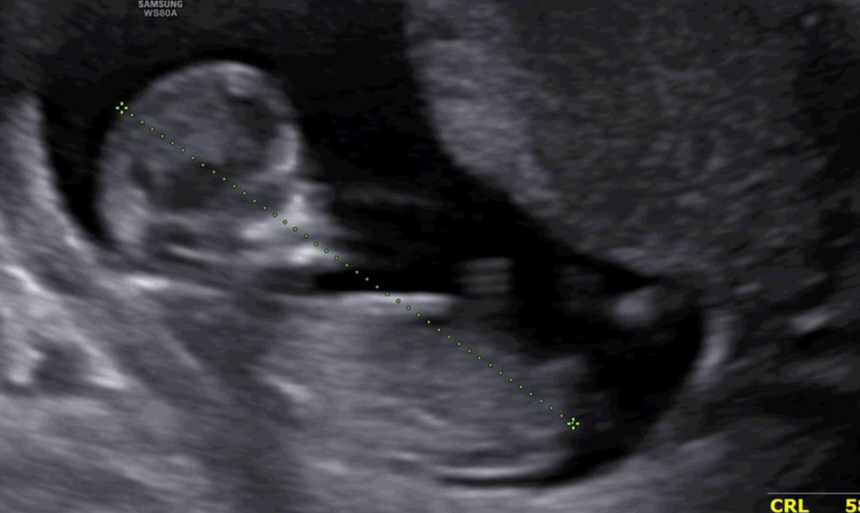

zariiii7070 مدیر استارتر عضویت: 1403/02/22 تعداد پست: 229 عنوان کسی از رو عکس جنین میتونه جنسینت رو تشخیص بده 119 بازدید | 26 پست امروز | 14:42 0 نفر لایک کرده اند ... گزارش تاپیک نامناسب

zariiii7070 مدیر استارتر عضویت: 1403/02/22 تعداد پست: 229 به شما هم احتمالی جنسیت رو گفتن؟ ب من گفت شاید دختر باشه